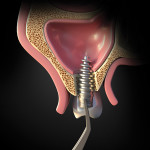

Using the OPG of the sinus, the clinician examined the site of displacement and detected the implant/abutment and determined it to be apically located. The patient was asked to move his head in different directions. Two successive OPG images were then taken to determine that the implant/abutment was not attached to the sinus wall or located close to the ostium; this was apparent because the implant/abutment position changed when the patient moved his head in various directions (Figure 2). It was then decided to retrieve the implant/abutment from the sinus by using a lateral window approach.

The location of the implant/abutment was determined by comparing an initial OPG with two others taken after lateral and vertical head movements. It was then determined that the implant/abutment was mobile and located close to the sinus floor. (The authors note that with regard to the use of the two successive OPG images, this approach yielded far less radiation exposure than two cone-beam computed tomography [CBCT] scans would have, and that one limited-field CBCT scan might not have shown positional movement of the implant. Additionally, the two OPG scans were easier to take and analyze than periapical x-rays, which may not have shown enough of the implant position and sinus.)